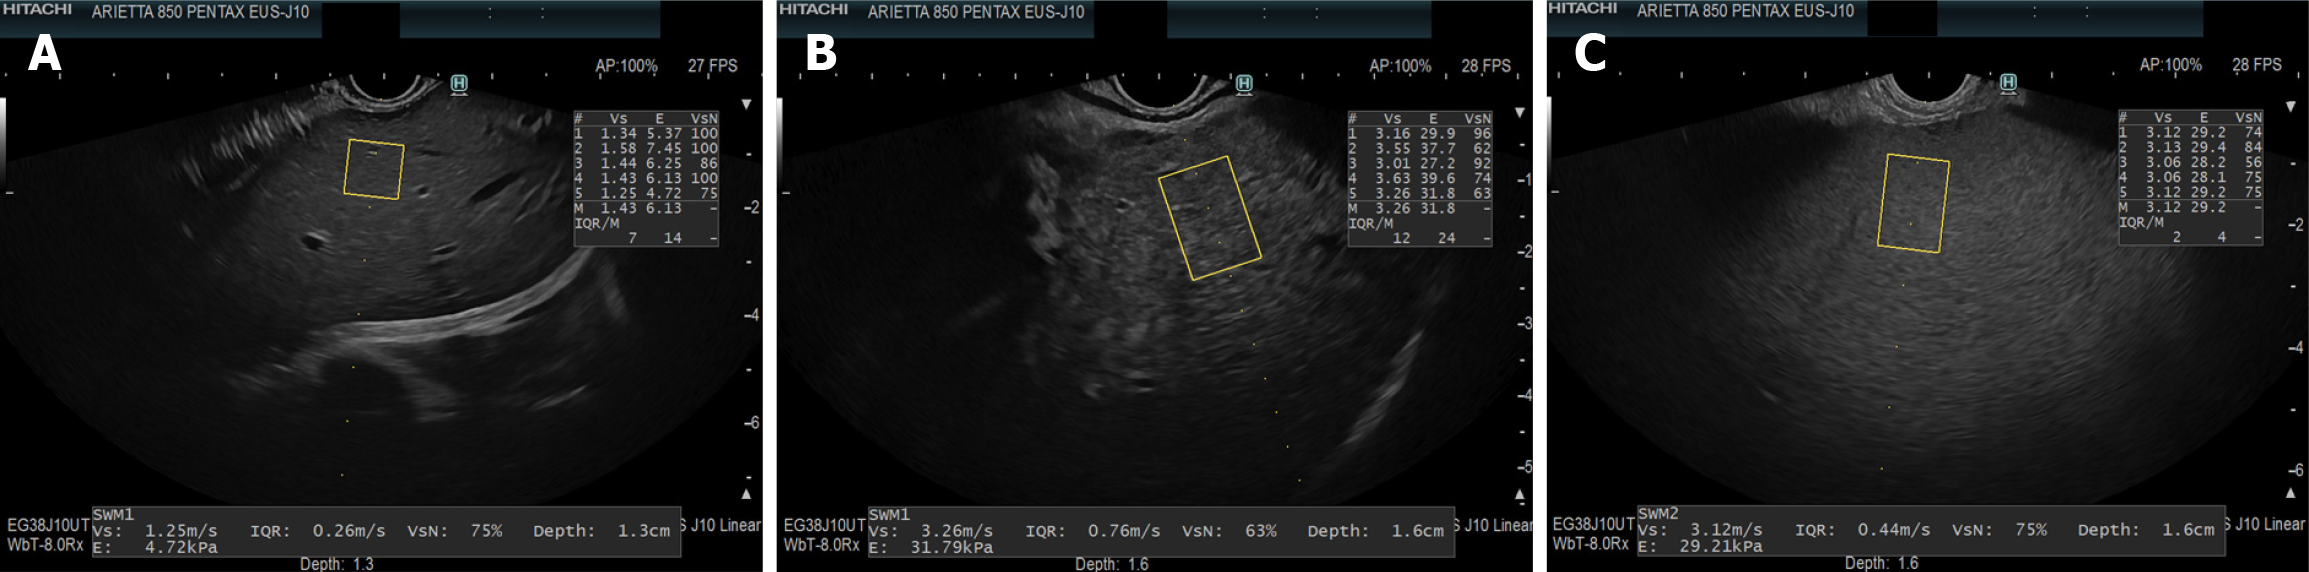

Figure 1 Endoscopic ultrasound-guided shear wave elastography images.

A: Normal pancreas; B: Chronic pancreatitis; C: Pancreatic cancer. In endoscopic ultrasound-guided shear wave elastography, shear wave velocity values were similar in normal parenchyma and chronic pancreatitis, but markedly higher in pancreatic cancer. The net effective shear wave velocity shows a decreasing trend across these conditions, reflecting increasing tissue heterogeneity and stiffness.